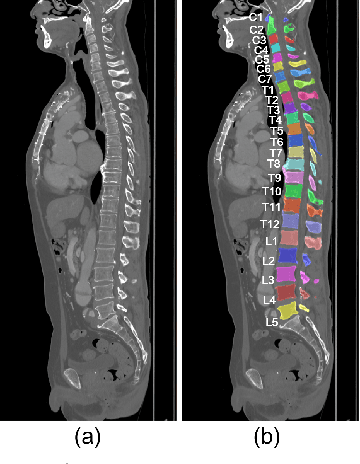

Abstract:This paper presents a method for automatic segmentation, localization, and identification of vertebrae in arbitrary 3D CT images. Many previous works do not perform the three tasks simultaneously even though requiring a priori knowledge of which part of the anatomy is visible in the 3D CT images. Our method tackles all these tasks in a single multi-stage framework without any assumptions. In the first stage, we train a 3D Fully Convolutional Networks to find the bounding boxes of the cervical, thoracic, and lumbar vertebrae. In the second stage, we train an iterative 3D Fully Convolutional Networks to segment individual vertebrae in the bounding box. The input to the second networks have an auxiliary channel in addition to the 3D CT images. Given the segmented vertebra regions in the auxiliary channel, the networks output the next vertebra. The proposed method is evaluated in terms of segmentation, localization, and identification accuracy with two public datasets of 15 3D CT images from the MICCAI CSI 2014 workshop challenge and 302 3D CT images with various pathologies introduced in [1]. Our method achieved a mean Dice score of 96%, a mean localization error of 8.3 mm, and a mean identification rate of 84%. In summary, our method achieved better performance than all existing works in all the three metrics.